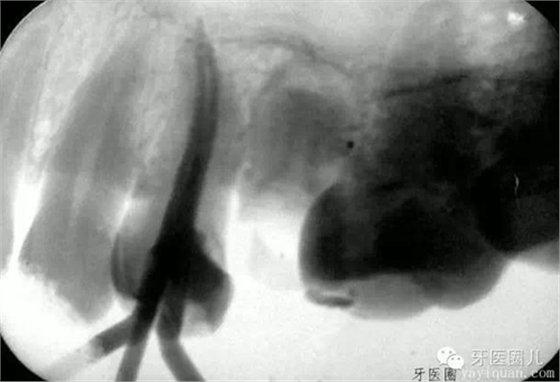

G鉆:低速手機(jī)上使用,細(xì)長(zhǎng)的頸部刃部短,頂端有安全鈍頭,1--6號(hào)刃部直徑0.5-1.5MM。長(zhǎng)度為32mm和28mm兩種,前者一般用于前牙,后者一般用于后牙(如果想做的漂亮這東西是個(gè)很好的利器稍后詳細(xì)介紹)。

3.用G鉆制造錐度:因?yàn)闆](méi)有鎳鈦的大錐度的擴(kuò)大針?biāo)訥鉆的使用就是最好的辦法啦。

我的使用順序是1--5號(hào)

根據(jù)根管的彎曲程度 1號(hào)大約是進(jìn)入到根管的16MM左右 ,1--3號(hào)然后每大一個(gè)號(hào)要退后2MM,

1號(hào) 2號(hào) 3號(hào)

4號(hào)進(jìn)入根管口下2~3mm,5號(hào)6號(hào)僅作根管口以上部分預(yù)備,便于髓腔與根管口形成直線通道

4號(hào) 5號(hào) 6號(hào)